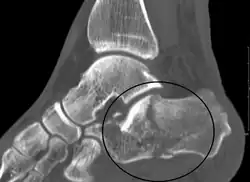

A fractured calcaneus as seen on CT

Conventional radiography is usually the initial assessment tool when a calcaneal fracture is suspected. Recommended x-ray views are (a) axial, (b) anteroposterior, (c) oblique and (d) views with dorsiflexion and internal rotation of the foot. However, conventional radiography is limited for visualization of calcaneal anatomy, especially at the subtalar joint. A CT scan is currently the imaging study of choice for evaluating calcaneal injury and has substituted conventional radiography in the classification of calcaneal fractures.[13] Axial and coronal views are obtained for proper visualization of the calcaneus, subtalar, calcaneocuboid and talonavicular joints.